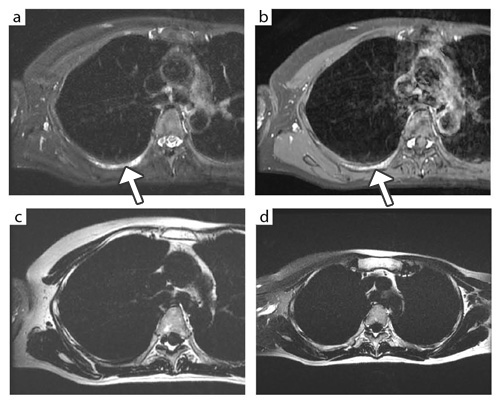

図4 IDEALによる胸郭の脂肪抑制画像

乳がんの肋骨転移が疑われた症例。右第6肋骨の背側部に,IDEALの脂肪抑制T2強調像(a)で高信号,IDEALの脂肪抑制造影T1強調像(b)で強く造影される病変(↑)が認められる。cは従来の脂肪抑制法による同一断面の脂肪抑制T2強調像であるが,肺の空気の影響で脂肪抑制が不均一になり,病変はほとんど指摘できなかった。頭側の断面(d)では,右前胸部から腋窩部に脂肪抑制による信号低下が見られる。